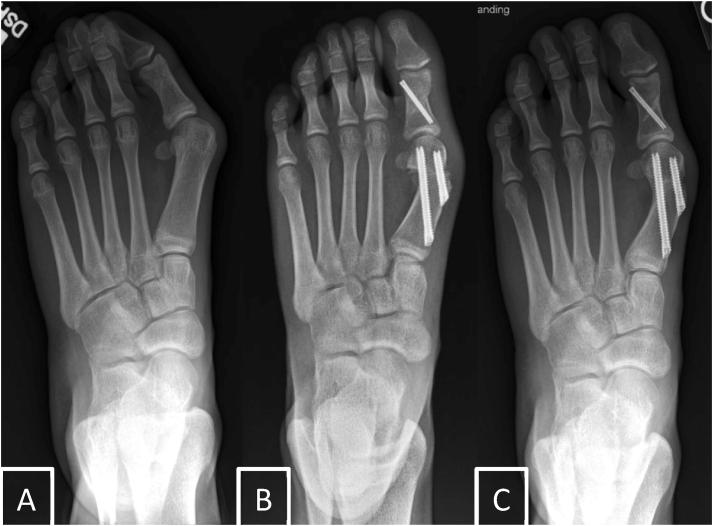

In adults, minimally invasive surgery for surgical treatment of hallux valgus has become increasingly popular, with a growing body of literature showing safety and effectiveness comparable to open surgery. Minimally invasive techniques for the treatment of juvenile hallux valgus include Bosch, Reverdin-Isham, Chevron, Endolog, distal soft tissue release, and hemiepiphysiodesis procedures. Data comparing minimally invasive and open surgery for the treatment of juvenile hallux valgus in children and adolescents are limited. In this review, we provide an overview of juvenile hallux valgus, discuss the minimally invasive techniques available for surgical treatment, and review the data on safety and effectiveness associated with each technique. There is a need for larger-scale studies comparing minimally invasive and open surgery for the treatment of juvenile hallux valgus, as well as the development of a standardized set of clinical and radiographic outcomes to guide evidence-based surgical management of juvenile hallux valgus.

(1)Compared with data on managing hallux valgus in adults, information on the safety and effectiveness of minimally invasive surgery for treating juvenile hallux valgus is limited.(2)Minimally invasive techniques for treating juvenile hallux valgus include Bosch, Reverdin-Isham, Chevron, Endolog, distal soft tissue release, and hemiepiphysiodesis procedures.(3)In total, 10 studies have assessed outcomes, demonstrating varying degrees of radiographic and clinical improvement along with complication rates.(4)Future large-scale comparative studies and standardized outcomes are essential for informing evidence-based surgical management of juvenile hallux valgus.